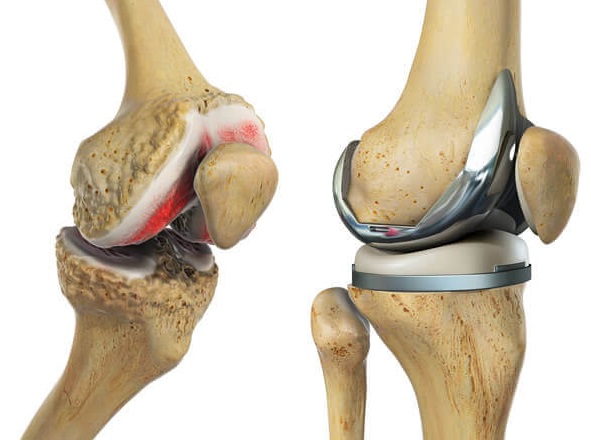

What is Knee Replacement Surgery?

Knee replacement, or knee arthroplasty, is a surgical procedure where a damaged or arthritic knee joint is replaced with a prosthetic implant. This procedure is recommended for individuals suffering from chronic knee pain due to arthritis, sports injuries, or degenerative conditions. Dr. Lokesh Yogi and his team at Jaipur Ortho are leaders in minimally invasive knee replacement surgery, offering precise treatment plans for faster recovery and long-term success.